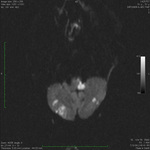

ინფარქტი დორსოლატერალურ მედულაში, ნათხემში ინფარქტის გაფანტულ კერებთან ერთად, როგორც ჩანს დიფუზურ-შეწონილ მრტ გამოსახულებაზე

ექიმი ს.ჰ. საბრამონის კოლექციიდან; გამოყენებულია მფლობელის ნებართვით